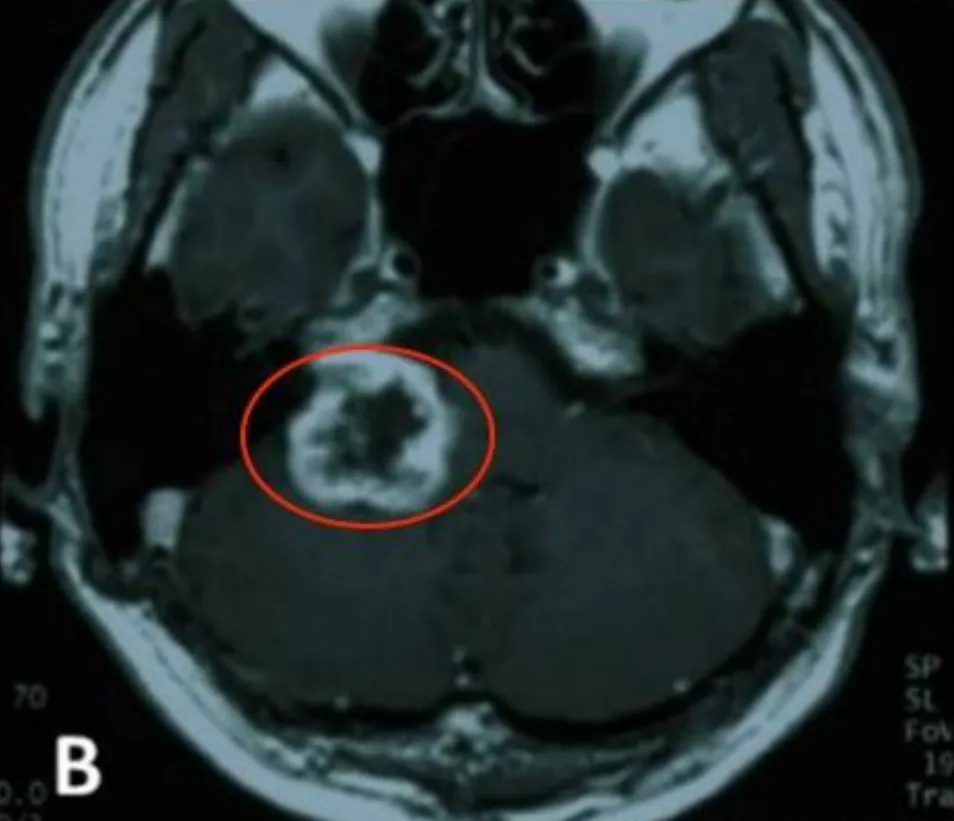

患者为54岁男性,右利手,家族中无神经纤维瘤病史。2003年,他开始出现右侧听力进行性下降及眩晕,纯音听阈检测显示右耳听阈58.5dB,符合单侧听神经功能受损的典型表现。影像学检查提示右侧桥小脑角区存在占位性病变,肿瘤已侵入内耳道,影像特征与前庭神经鞘瘤相符。

2004年5月,患者在外院接受了右侧乙状窦后入路肿瘤切除手术。术中发现肿瘤质地坚硬、血供较为丰富,与周围组织粘连紧密,因此仅完成了次全切除。术后病理诊断证实为良性前庭神经鞘瘤。